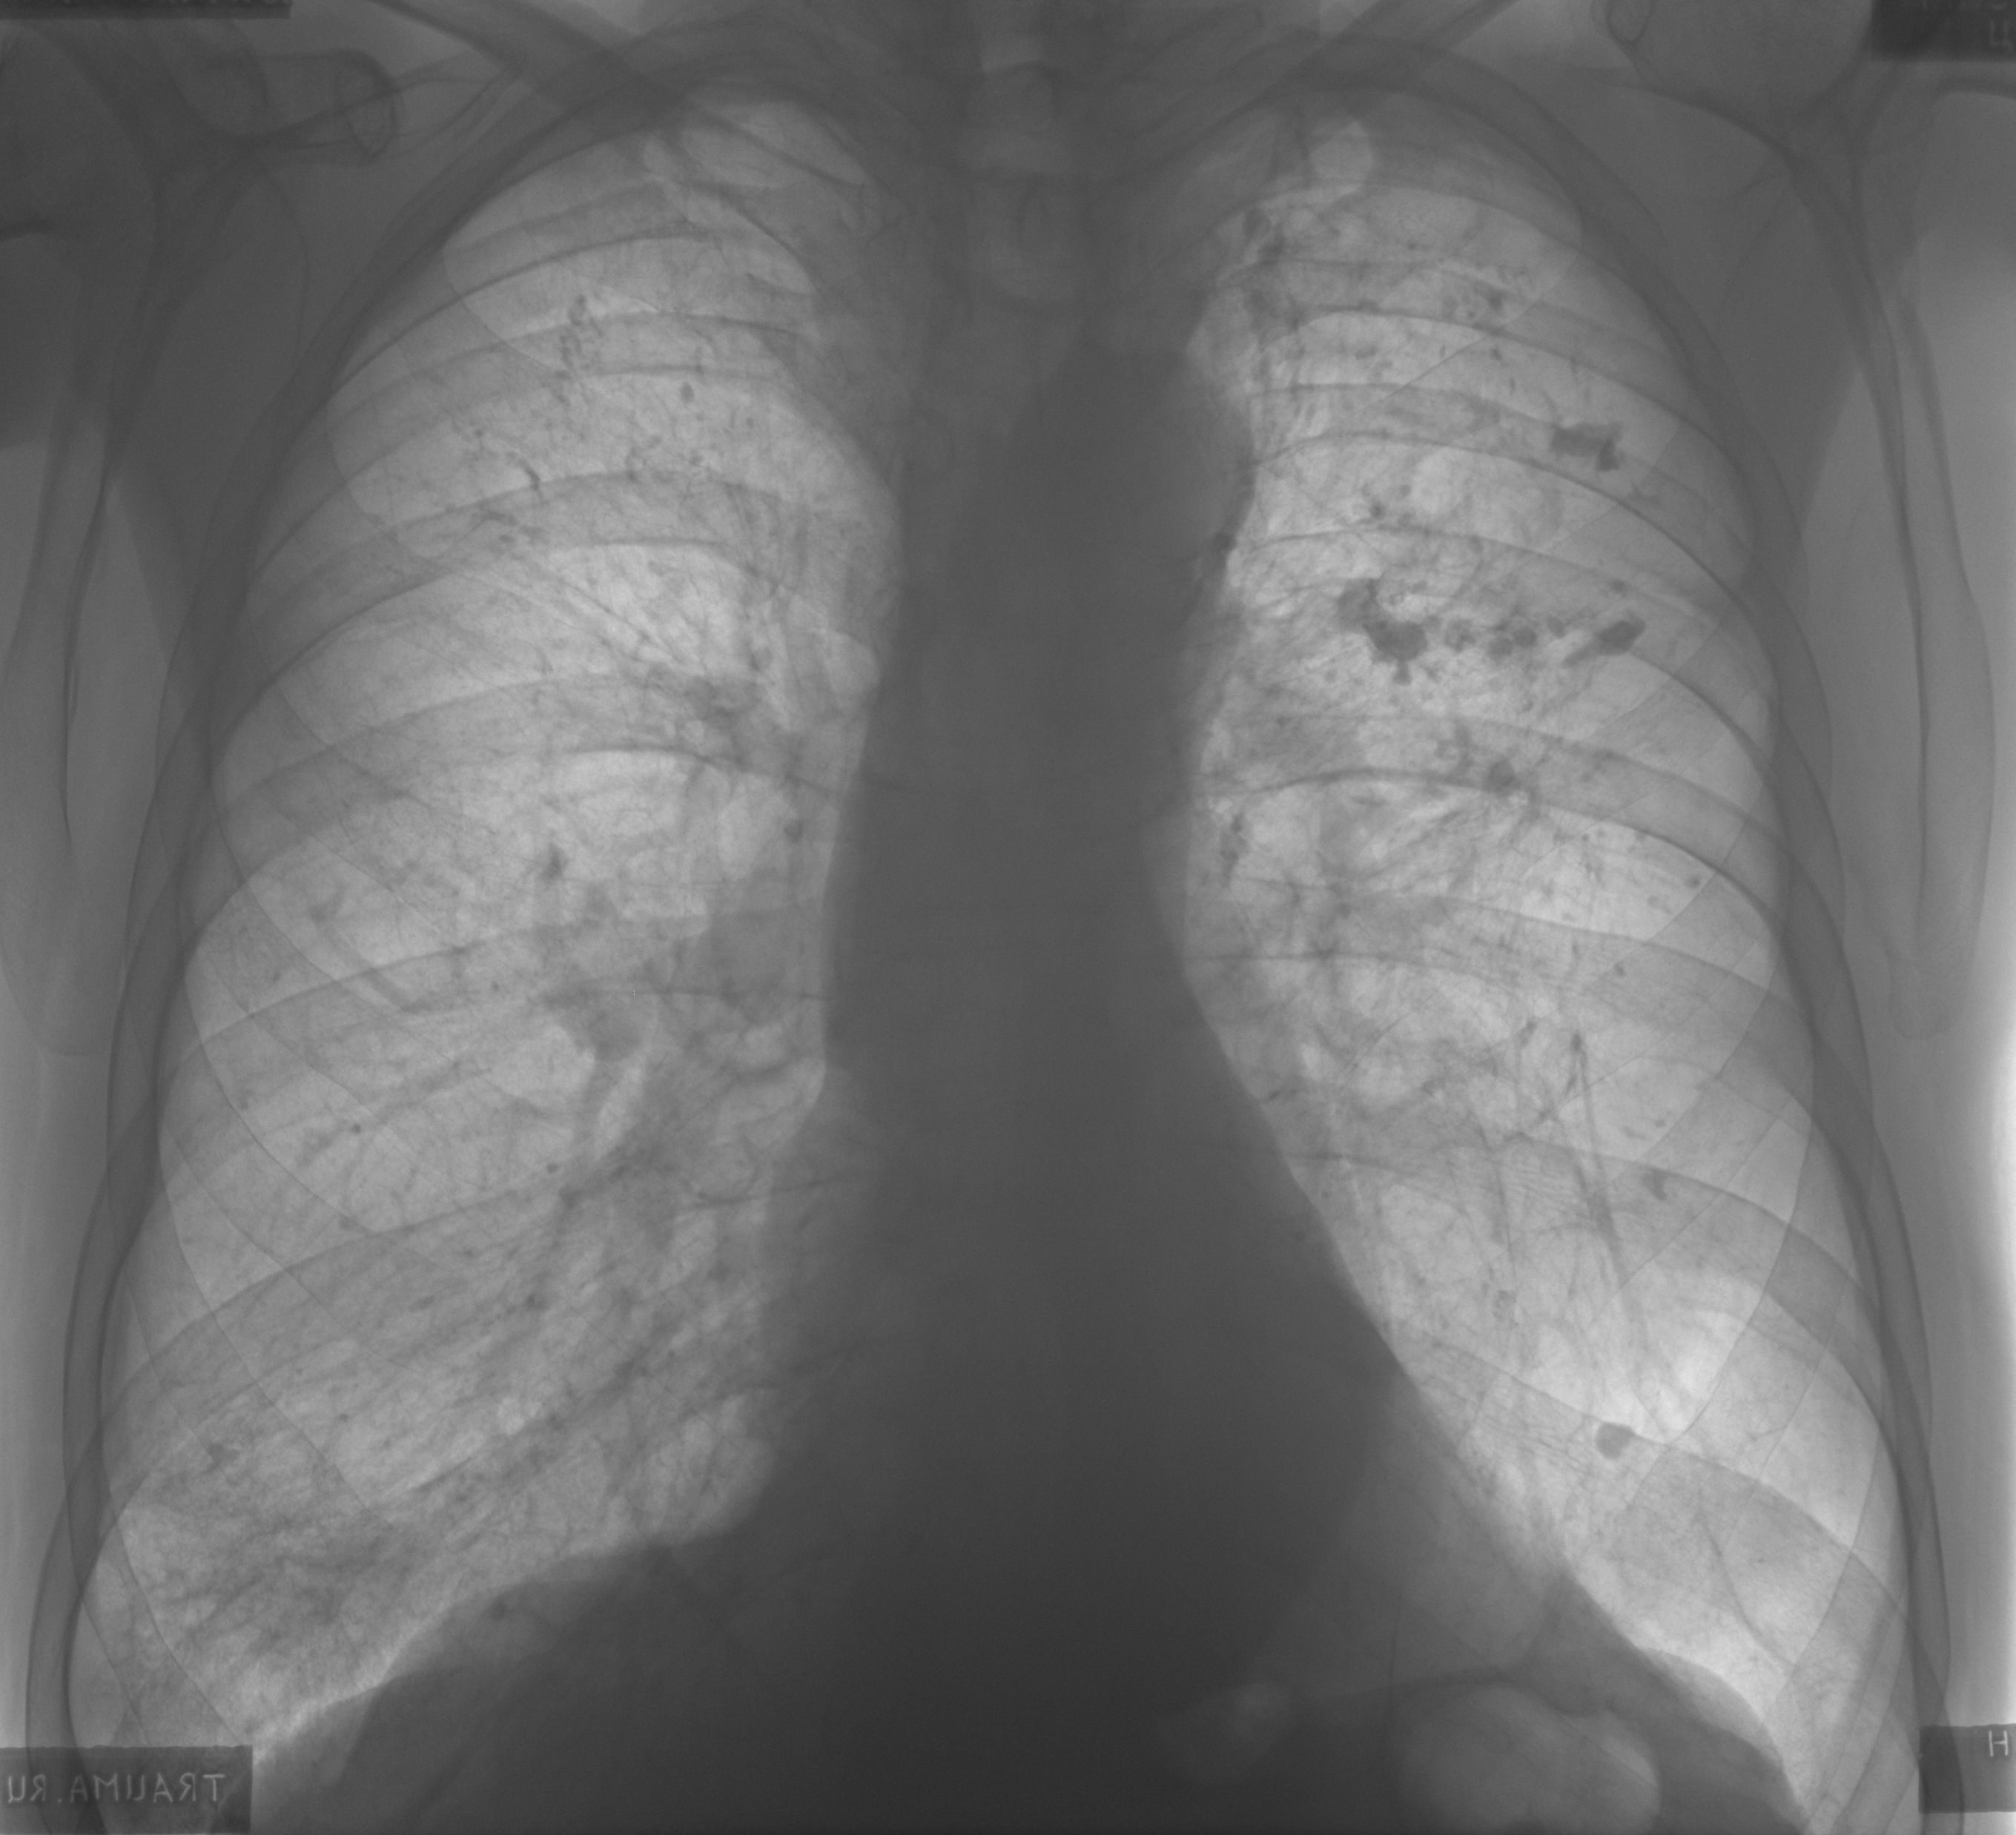

Снимок легких при туберкулезе является важным методом диагностики этого заболевания. На рентгеновских снимках можно увидеть изменения в легких, которые свойственны туберкулезу.

Диссеминированный туберкулез на рентгенограмме

Диссеминированный туберкулез рентген

Диссеминированный туберкулёз лёгких рентген

Диссеминированный туберкулез

Милиарный диссеминированный туберкулез

Фотографии снимков легких при туберкулезе

В данной статье представлены многочисленные фотографии снимков легких при туберкулезе, чтобы помочь вам понять, как выглядят изменения легких на рентгеновских снимках при этом заболевании.